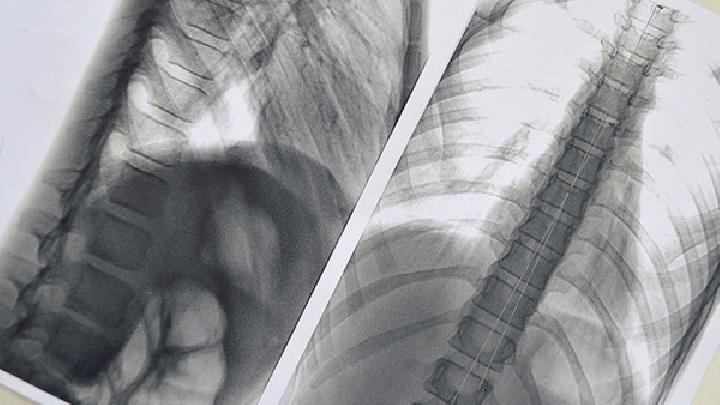

近50多年来,世界各国特别是工业发达国家,肺癌的发病率和病死率均迅速上升,死于癌病的男性病人中肺癌已居首位。因此,肺癌的诊断也成为重要的身体检查项目。

肺癌是大家并不陌生的一种疾病,很多人听说过此病,但是并不了解,该病是肺部细胞癌变增生引起的,吸烟是诱发其发病的主要因素,生活中要注意及时防治此病。下面就一起来看看肺癌的诊断有哪些方法。

肺癌,这现在已经逐渐成为我们生活中的一种常见癌症了,每年因为这种疾病夺去生命的人数有很多。那么,肺癌如何诊断呢?我们需要有一定的了解,才能更好的帮助我们发现疾病,及时的进行控制。